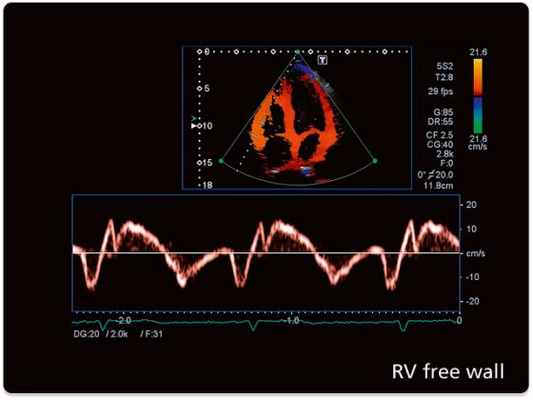

Современные технологии (тканевой допплер, контрасты) позволяют во много раз повысить информативность исследования, особенно, у больных с патологией миокарда.

в) Спектральный допплеровский сигнал. Спектральный допплеровский сигнал при импульсно-волновом режиме исследования воспроизводит распределение скоростей в контрольном объеме, причем чем шире допплеровский спектр, тем сильнее различаются скорости движущихся объектов (например, эритроцитов) в пределах этого контрольного объема. Амплитуда сигнала, т.е. яркость каждой точки спектра, приблизительно пропорциональна количеству отражающих объектов в пределах контрольного объема, движущихся с соответствующей скоростью. Наиболее яркая область спектрального сигнала при импульсной допплерографии обозначается как «модальная» скорость.

M-режим (M – motion) – режим одномерного сканирования с получением развертки в реальном масштабе времени, который применяется для регистрации пространственного положения исследуемых объектов во времени (отслеживания движения исследуемых структур). Наиболее часто данный режим используется при кардиологических исследованиях совместно с B-режимом, где B-режим используют для навигации.